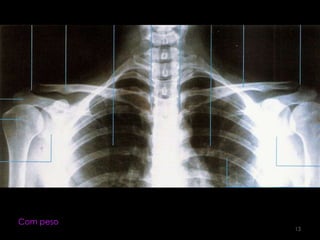

Incidência AP: Articulação acromioclavivular  bilateral (com e sem peso) 10

Sem peso12

Com peso13